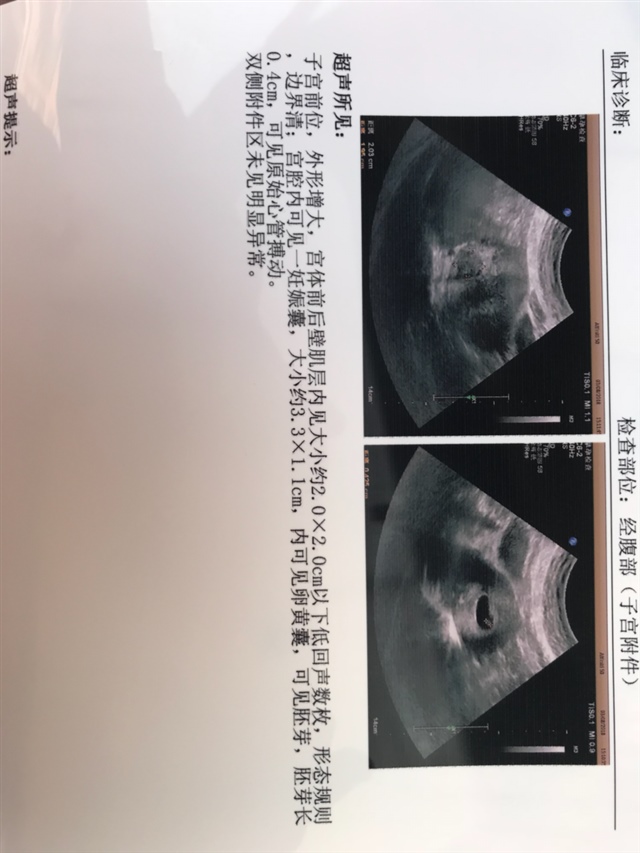

这个肌瘤医生说是常见的,我也不知道怎么办,因为这次怀孕是二胎,生第一个宝宝的时候就没有肌瘤。

肌瘤